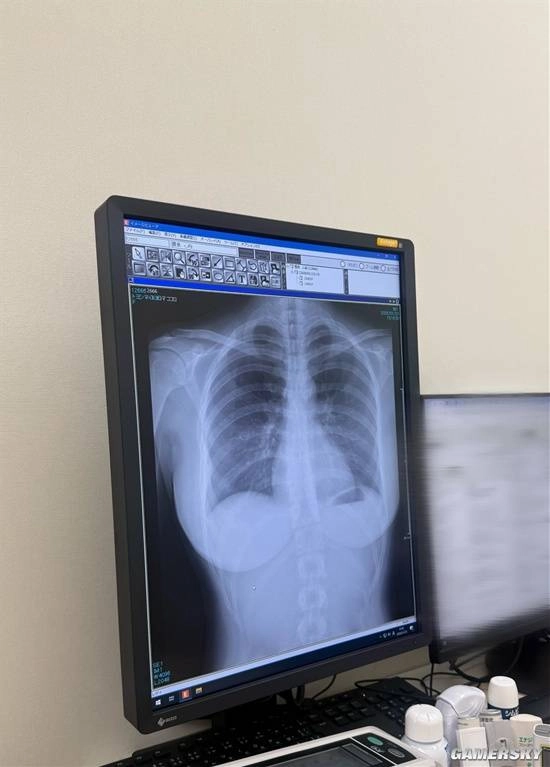

近期,她一个别出心裁的举动再次吸引了众人目光:在社交平台上公开了自己的肺部X光片。这张影像不仅展现了其健康状况,更因为日本写真偶像极少公开此类个人医疗信息而引发热议。

写真偶像直接公开X光片的情况为何极为少见?一来这涉及到医疗法规层面的问题,二来专业人士可以借助这类影像对胸部构造进行观察,进而间接判断其是否属于纯天然、未经过整形的状态。

也有人从专业角度对其肺部情况给出了点评:“这张胸部正位X光片呈现出的肺部状态非常好。两侧肺野都很清晰,没有发现浸润、结节的情况,也不存在胸腔积水问题。心脏的轮廓大小正常,胸廓骨骼方面没有看到骨折或者其他异常表现。”